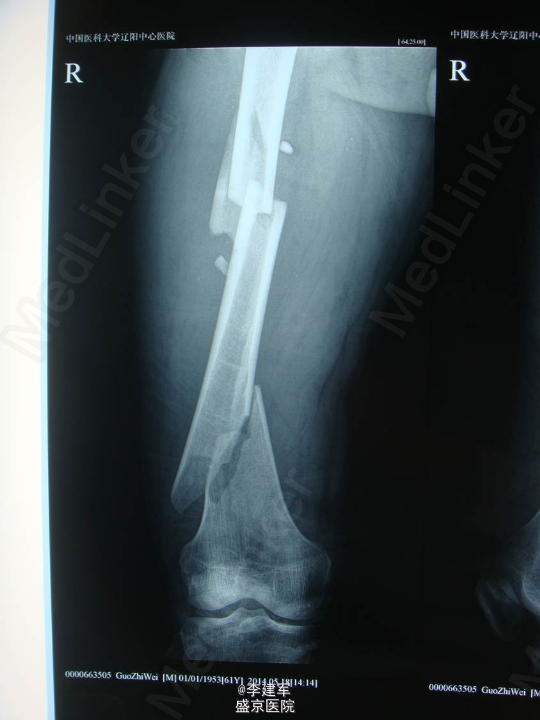

主诉:摔倒后右大腿疼痛肿胀活动受限5小时 现病史:患者家属自述骑自行车自行摔倒,摔倒后右大腿疼痛肿胀,活动受限,伤后患者昏迷约一小时,急诊送入当地医院,DR(当地医院)提示右股骨干骨折,当地医院给予患肢皮牵引固定等对症治疗。今日患者为求进一步手术治疗来我院治疗。门诊以“右股骨干骨折”为诊断收入院。患者病来一般状态可,生命体征平稳,无发热,饮食睡眠可,二便正常。

专科查体:患者平车推入病房,右下肢短缩屈曲中,右大腿疼痛,肿胀明显,可触及反常活动及骨擦感,纵向叩击痛阳性。右大腿外侧可见皮肤瘀斑,右足背动脉搏动正常,足趾活动可,皮肤感觉较健侧无明显异常。

诊断:右股骨干粉碎性骨折 患者右股骨干粉碎性骨折,拟行右股骨干骨折闭合复位内固定术。